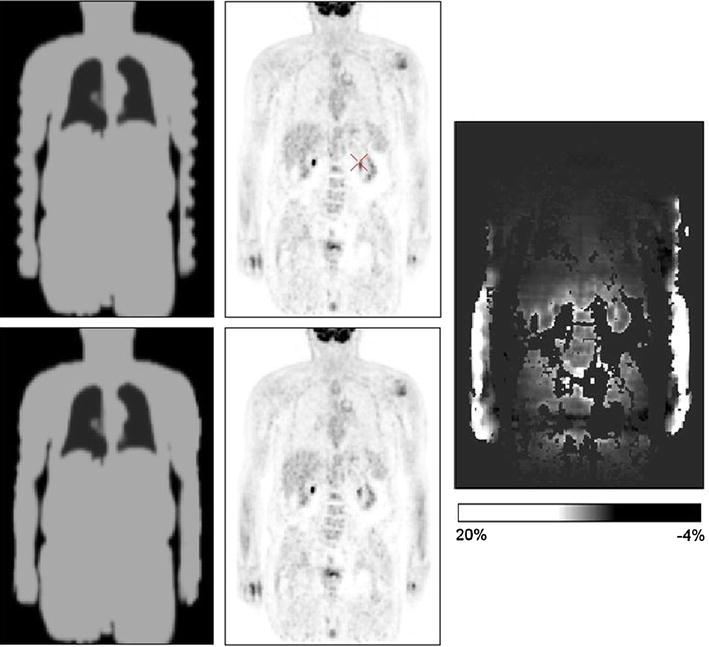

The arms are not completely covered in the whole-body MR scan leading to truncation artefacts in the attenuation map image (top left), which were successfully compensated (bottom left). The corresponding reconstructed PET images are shown in the middle column. The relative percentage difference image (right) shows the greatest changes around the arms, and moderate changes inside the trunk with the highest changes observed at surfaces of anatomical structures [35] (courtesy of Z. Hu)